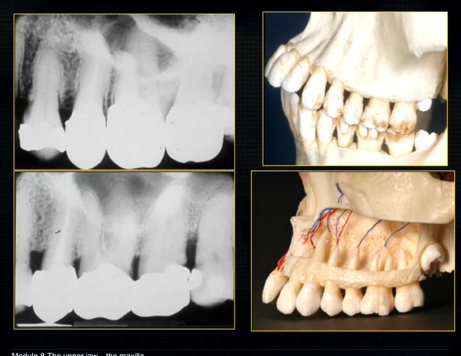

when the thin, surface bone of the maxilla is removed …

can see the roots of the teeth as they are positioned in the alveolar part of the maxilla

the alveolar bone has an internal trabecular, honeycomb appearance - wide enough to envelope all the roots of the posterior teeth

mandible varies in cross sectional thickness

left hand side of the mandible buccal surface has been removed

roots of the teeth protrude in the underlying trabecular bone

inferior dental nerve

mental nerve - coming out of the mental foramen

reveals honeycombed pattern of trabecular bone

dense outline of the individual sockets of the teeth

cortical bone which forms the lower border